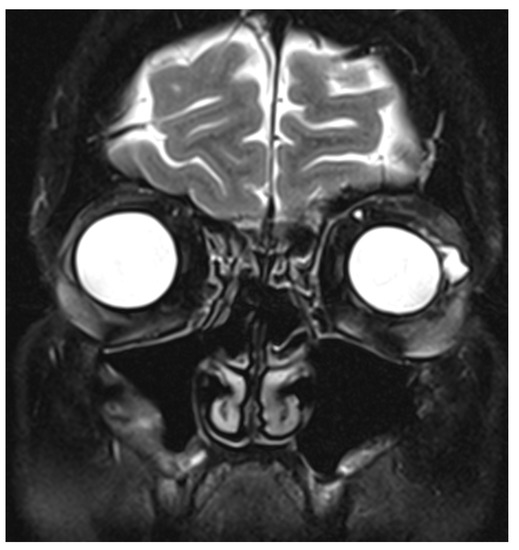

2. Case Report